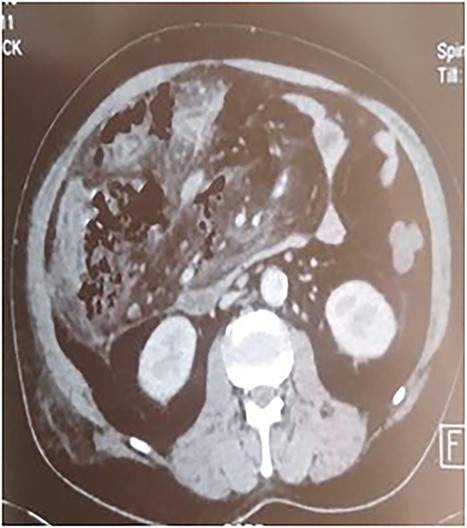

A 53-year-old man with no known medical history was admitted to the hospital because of epigastric pain persisting for 24 h, accompanied by weakness. Physical examination revealed a temperature of 39°C, severe dehydration, poor peripheral perfusion, a pulse of 110 bpm, blood pressure at 10/6 mm/Hg, a painful and tympanic abdomen without peristalsis, with tenderness over the epigastric region. Laboratory tests showed a lipase level of 667 U/l, sodium at 140 mmol/l, potassium at 4.5 mmol/l, creatinine at 106 μmol/l, urea at 6.5 mmol/l, alanine aminotransferase at 161 U/l, aspartate aminotransferase at 85 U/l, an elevated leukocyte count at 29,3 × 109/l. Abdominal CT with contrast revealed pancreatic necrosis with gas surrounding the pancreas, as well as pneumoperitoneum and in the right anterior pararenal space. Thickening of the mesentery root with lymph node enlargement (Figs 1–3).